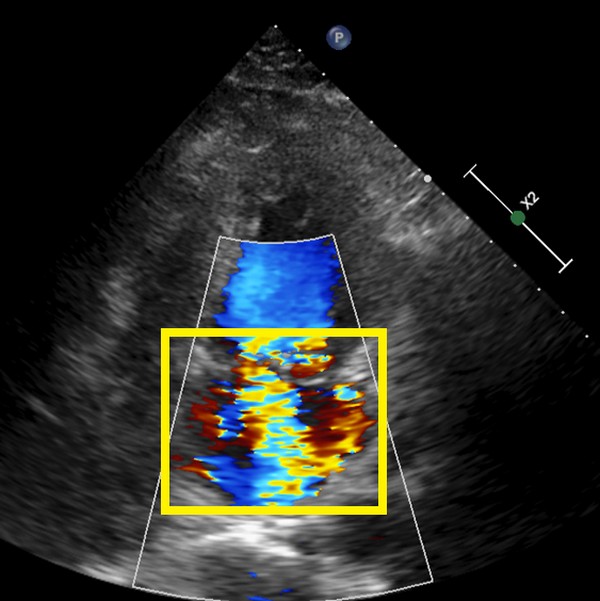

▲僧帽瓣逆流。

二尖瓣又稱僧帽瓣,是位於左心房與左心室間的瓣膜,可以控制血液流向。左心室是心臟輸出血液最重要的構造,收縮時二尖瓣會關閉,讓左心室將血液輸注至人體的大血管,供應全身組織,而逆流指的是左心室收縮時,二尖瓣無法完全緊閉,部分血液會倒流回左心房。羅崇祐醫師說明:「血液可以養活所有器官,但二尖瓣逆流會導致心輸出量大幅下降,進而造成嚴重的心因性休克和多重器官衰竭,倒退的血液則會造成囤積在肺部造成嚴重的肺水腫,危及生命。」